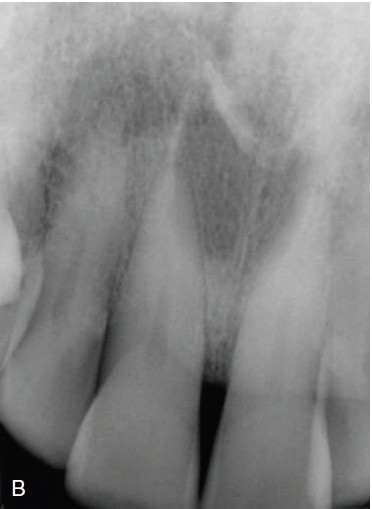

8 / 25

8. (Select ONE correct answer)

What is the most likely diagnosis for the lesion associated with tooth 3.8?